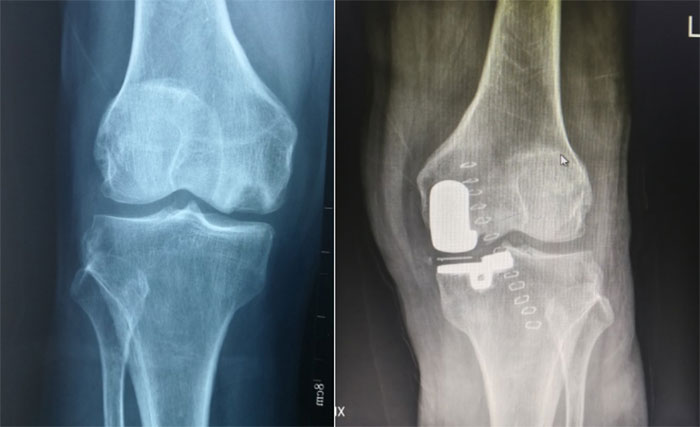

科室著重全力開展膝骨關(guān)節(jié)炎的“保膝治療”。關(guān)節(jié)炎早期的運(yùn)動處方,保守治療;局麻非止血帶條件下膝關(guān)節(jié)清理微創(chuàng)治療;關(guān)節(jié)鏡清理結(jié)合脛骨高位截骨(HTO)及單髁(UKA)置換是滄州市中心醫(yī)院運(yùn)動醫(yī)學(xué)科最具特色的階梯治療方案。肩關(guān)節(jié)鏡微創(chuàng)技術(shù)在省內(nèi)亦處于先進(jìn)行列, 2021年肩袖損傷,肩關(guān)節(jié)骨折、脫位等肩部的關(guān)節(jié)鏡手術(shù)即已達(dá)到300余例。

肘關(guān)節(jié)鏡治療關(guān)節(jié)僵硬術(shù)前VS術(shù)后

單踝置換術(shù)前VS術(shù)后